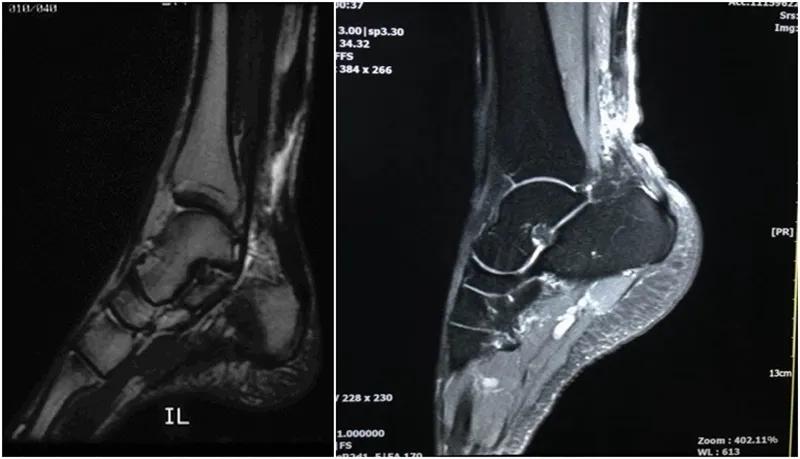

MRI:常用于评估肌肉骨骼的问题,当怀疑跟腱断裂且无高质量诊断性超声可用的情况下是首选检查方法。MRI在检查跟腱部分撕裂时可以提供更多的解剖细节和更高的准确性。

跟腱撕裂MRI评价标准:

(1)完全撕裂:跟腱增粗,腱束分离,局部T1WI、T2WI信号均匀增高或局部信号不均匀增高,腱束重叠交织但不连续。

(2)部分撕裂:跟腱增粗,局部T1WI、T2WI信号不均匀增高,内见部分连续的腱束影。